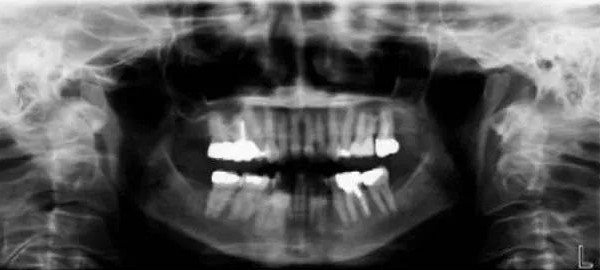

全景片是什么?全景片就是可以在一张胶片上可以完整、清晰地显示上颌骨、下颌骨全貌,上下颌牙列情况,牙槽骨情况能清晰显示上颌窦腔、窦壁、窦底情况,以及颞颌关节情况并对颌骨周围疾病的诊断提供帮助。

因为全景片可以确定测定牙齿倾斜角度、牙周软组织情况、牙根情况、牙槽骨质情况,解剖形态的精确测量为医生术前的诊断分析与设计提供全景样图像依据,口腔医生借此能更好地为患者设计治疗方案。

拍摄全景片是口腔治疗之前很重要的一个检查过程,医生通过全景片可以观察到牙齿的健康状况,是否有隐形龋齿、埋伏阻生牙、多生牙、牙槽骨吸收、牙龈萎缩、口腔内是否有瘤体等。在做牙齿种植、牙齿矫正、牙齿修复、智齿拔除等之前均需要拍摄口腔全景片。

①牙齿的解剖结构、密度,牙周状况的检查。②埋藏牙定位及周边相邻关系判断。③牙齿发育情况判断。④牙齿矫正前的病例分析、测量,指导矫正方案的制定。⑤种植前牙槽骨的质、量的评价及种植体大小、长短的确定。

⑥牙列缺失复杂修复前基牙的评估。⑦头面部外伤、骨折的诊断。⑧根管充填、镶牙、种植、矫正效果的复查、评估。⑨智齿拔除等外科手术方案制定和风险评估。⑩头、面部肿瘤、囊肿的筛查,鉴别。